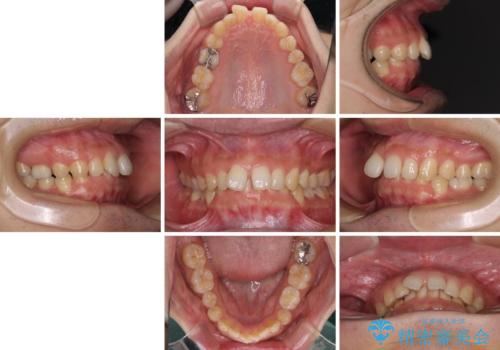

- 治療期間

- 2年7ヶ月

- 前歯の隙間を気にして来院された患者様です。

下顎前歯が見えなくなるくらいに深い咬み合わせであり、さらに上顎の正中が開くほど下の前歯が突き上げている状態でした。

奥歯は手前に倒れてしまっているため、後方に起き上がらせることで深い咬み合わせ・ディープバイトを改善する必要があります。

ディープバイトの方は項合力が強大であることが特徴のため、仕上がりを重要視して、ワイヤー装置にて矯正治療を行うこととしました。

右上と左下は永久歯が欠如しており、大きさの大きく異なる乳歯が残存していたため、奥歯の咬み合わせを構築するために苦労しました。

元々隙間の空いていた上顎の正中は、後戻りのリスクが高いため、下顎前歯同様ワイヤー固定を行いました。